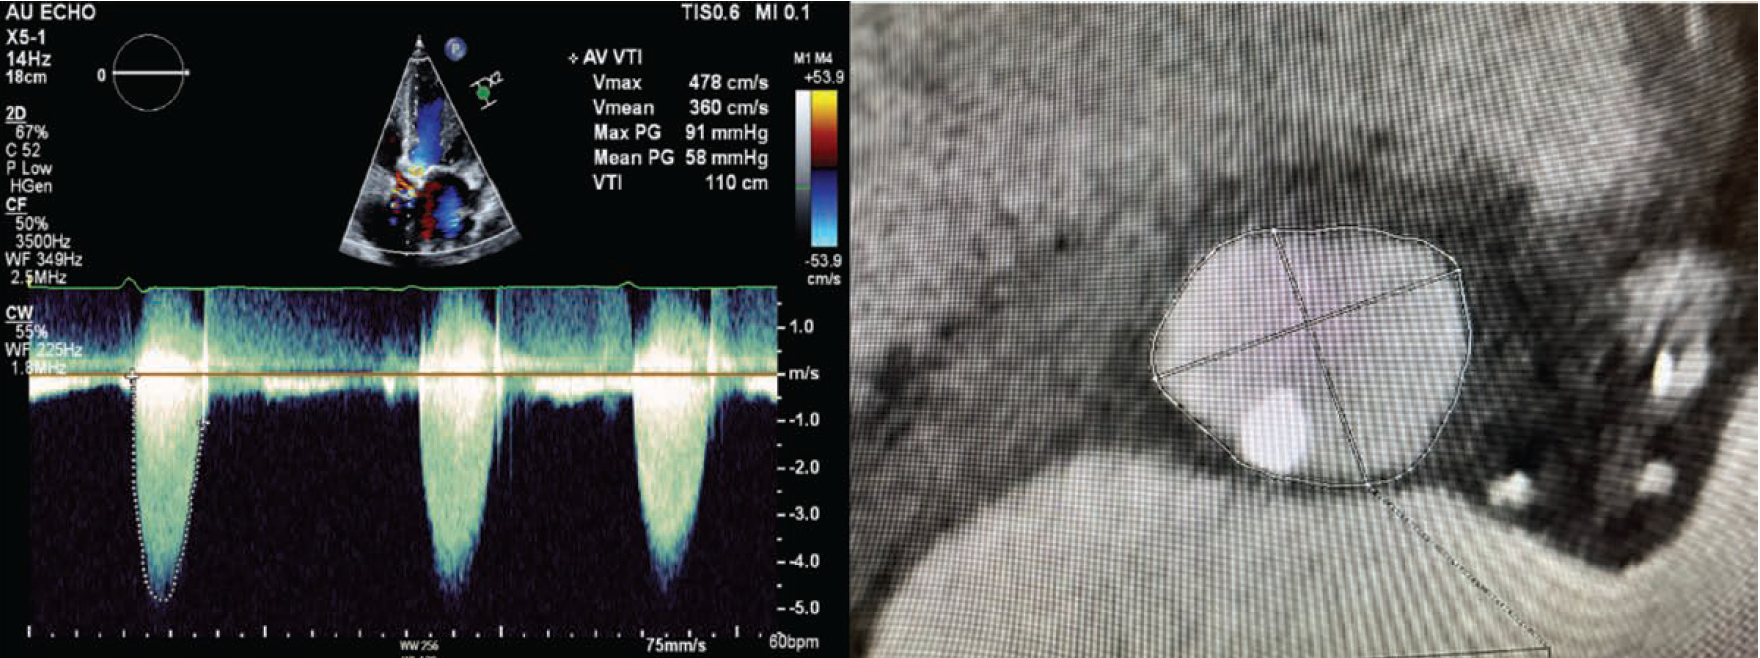

Transthoracic echocardiography (TTE) revealed an ejection fraction of 20%-25% and critically severe aortic stenosis (aortic valve area of 0.26 cm², mean pressure gradient of 58 mmHg, dimensionless index of 0.16, and peak aortic velocity of 4.7 m/s). Right and left heart catheterization indicated preserved cardiac output and mild coronary artery disease. Computed tomography (CT) angiography showed peripheral vasculature suitable for a femoral approach for TAVR, as well as severe calcification of the aortic valve with a calcium score of 5478. Furthermore, there was a prominent calcific nodule extending into the annulus and LVOT, and aortic annular area measured at 418 mm2 (Figure 1).